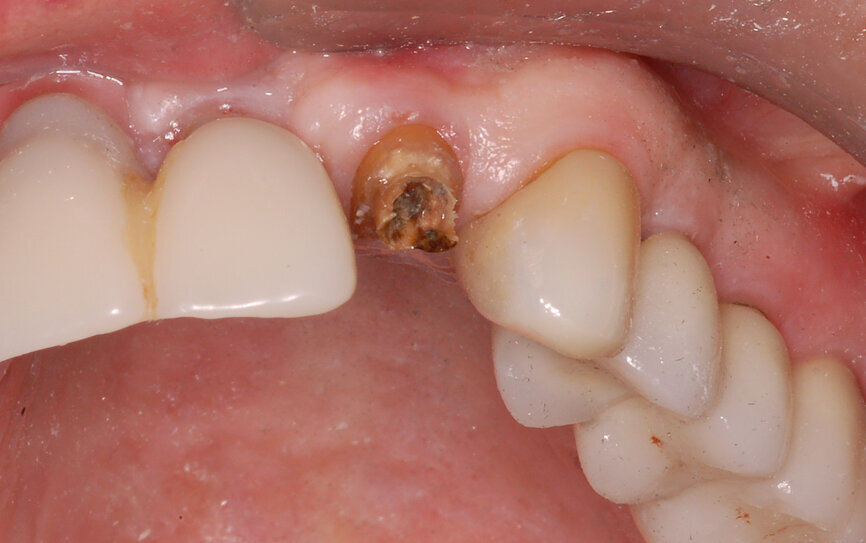

Fig. 1: The patient presented with a horizontally fractured clinical crown, an indication for a partial extraction therapy procedure.

One indication for PET is when a patient presents with a horizontally fractured clinical crown (Fig. 1). While a 2D radiograph will reveal the extent of the horizontal fracture, length of the remaining root and approximation of the bone apical to the root, there is not enough information to plan for a PET procedure. A CBCT scan is recommended in order to fully appreciate the root position within the alveolus and the potential difference between the trajectory of the bone and the trajectory of the root as can be visualised with a cross-sectional image (Fig. 2). Utilising interactive treatment planning software makes it possible to plan the initial drill path to accurately section the root to its apex (Fig. 3a). This can be accomplished by creating a custom implant design to match the diameter of the initial drill with an abutment projection in order to fully appreciate the trajectory through the clinical crown (Blue Sky Plan, Blue Sky Bio). It is important to visualise the root fragment that will remain in order to properly simulate the position of the implant in the alveolus (Fig. 3b). The apical portion of the implant can be positioned to gain stability in host bone using the Triangle of Bone. It is important to note that a cross-sectional slice may only be 0.125 mm in thickness based on the CBCT acquisition, and therefore all images in all views must be visualised to confirm the plan. Utilising 3D segmentation (separating objects by density values), it is possible to define each root and further assess the simulated position of the implant with a sagittal cut through the 3D reconstructed volume (Fig. 4).